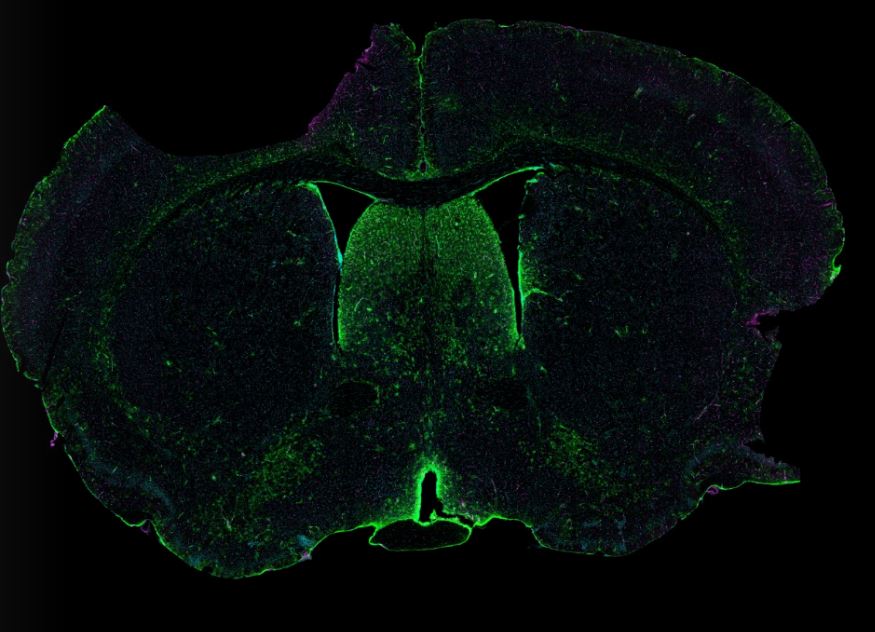

Nick Natale is a PhD candidate in the Department of Neuroscience who works in the laboratories of Dr. John Lukens and Dr. William Petri. Although SARS-CoV-2 is often described as a respiratory virus, Nick's research provides a different perspective of how SARS-CoV-2 invades the host. He investigates the neuroimmune underpinnings of coronavirus disease (COVID)-19-induced olfactory dysfunction. In the Biosafety Level 3 facility, Nick uses a mouse-adapted SARS-CoV-2 virus to recapitulate severe COVID-19 observed in humans and leverages spatial transcriptomics, immunofluorescence confocal microscopy, transgenic reporter mice, and olfactometry to assess alterations in the olfactory system during SARS-CoV-2 infection. As SARS-CoV-2 becomes increasingly acquainted with the mammalian olfactory system, this research pursuit will help prepare us for future sarbecovirus pandemics and the potential neurological-PASC (post-acute sequalae of SARS) epidemics that follow.